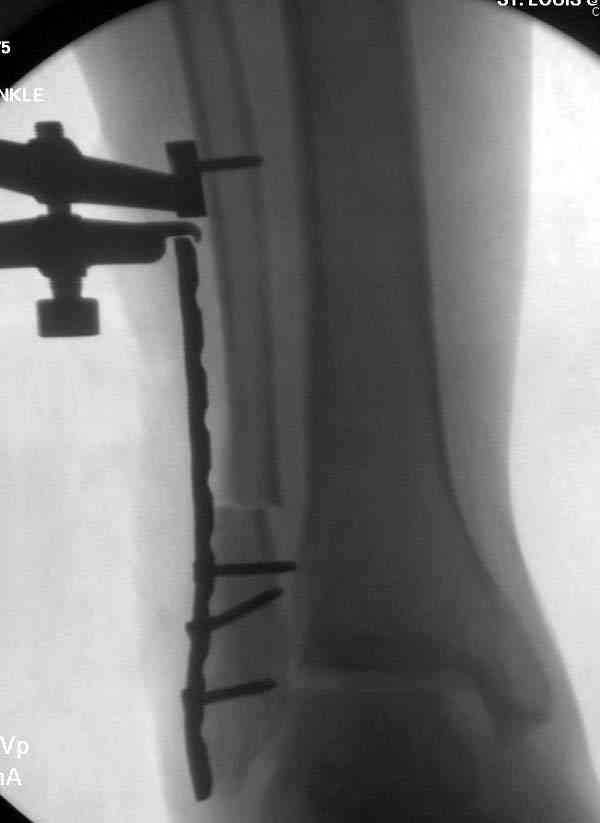

Здесь представлено решение похожей проблемы. Больной в течение года лечился консервативными мерами, и боли в голеностопе были основным показанием к операции.

Проведена обычная стандартная процедура по исправлению неудовлетворительного состояния голеностопного сустава, где кроме удлинения малоберцовой с применением compression tension device за проксимальный конец пластины, проведено замещение трикортикальным графтом из крыла, освобождение синдесмоза и медиальной щели от

фибротических масс с фиксацией.